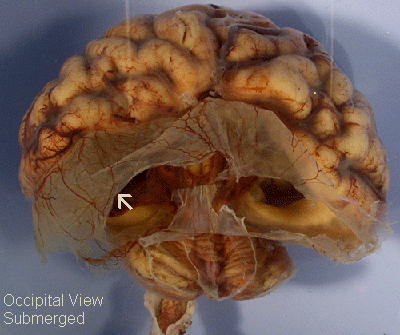

Holoprosencephaly: This image was taken when the brain was submerged in water which allowed the glial-ependymal seam to float. The thinness of this seam is best appreciated in this photo.